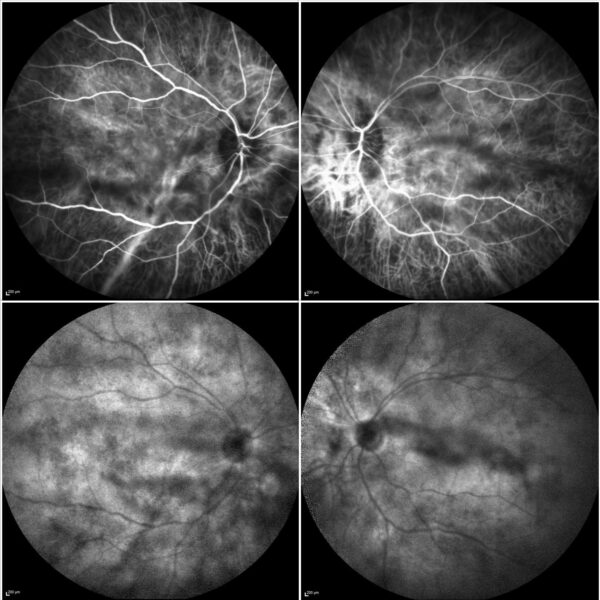

Indocyanine green angiography (ICG-A) showed prominent choroidal vessels in the early frames and multiple hypocyanescent spots in BE (Figure 3).

Figure 3: ICG-A (Spectralis, Heidelberg Engineering®) of both eyes displaying prominent choroidal vessels in the early frames (top) and numerous hypocyanescent spots (Dalén-Fuchs nodules) in the late frames (bottom).